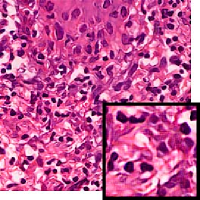

We demonstrate our WSI creation workflow on Leishmaniasis cases, as shown in Figures 1 and 4. An expert pathologist reviewed the cases and annotated granulomas as well as LD bodies on the stitched images and our generated images in Figure 4. To show generalizability of our approach, we also show results on core biopsies of breast, duodenum, stomach, liver, and lymph nodes (Figure 5).

| Breast | Duodenum | stomach | liver | lymph node | |||||